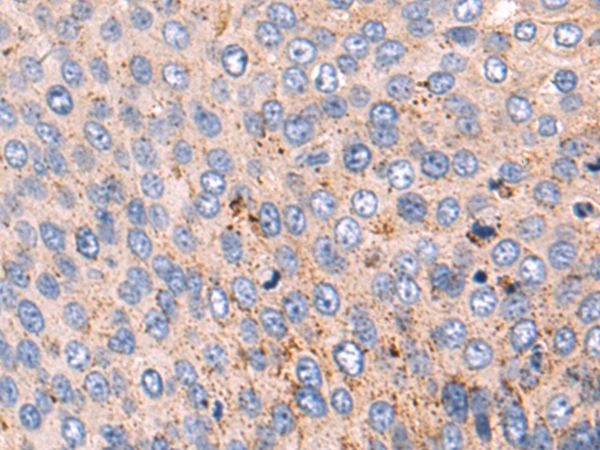

分类: 科研抗体货号: P06937别名: Ga55应用: IHC反应种属: Human, Mouse